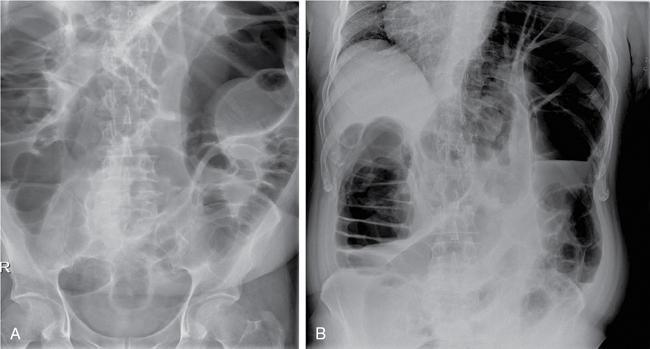

Plain abdominal radiograph

Kulbir Ahlawat, Ravi Chaudhary, Arvind Pandey, Anuj Bahl, Navni Garg, Sonam Shah, Sonali Sharma EMBRIOLOGY AND ANATOMY OF COLON Sonali Sharma A deep understanding of the development and the embryology of the colon is essential to understand the variety of the developmental anomalies related to the aberrations in the normal embryological processes (Table 8.4.1.1). Broadly the development of the colon can be summarized in three stages: The rate of growth of the embryo exceeds the growth rate of the yolk sac during the third and the fourth weeks of development. During the fifth week there is development of the omphalomesenteric duct or the Vitello intestinal duct or the yolk stalk which serves as a connection between the extraembryonic and the intraembryonic coelom (Fig. 8.4.1.1). The midgut at this point is divided into two equal length segments and the loop has its axis at the superior mesenteric artery (SMA). The apex is marked by the yolk stalk or the omphalomesenteric duct. There is a periarterial segment and the postarterial segment of the loop, the former starting at the foregut–midgut junction and ending at the apex. The postarterial segment lies between the apex and the midgut–hindgut junction. Eleventh week marks the beginning of the return of the postarterial segment of the gut, which continues to rotate in front and then to the right of the SMA. By the twelfth week the colon completes a 270-degree anticlockwise rotation with prior 90 degrees during herniation, and a further 180-degree counterclockwise rotation during the reduction of the postarterial segment. The prearterial segment gives rise to: Postpapillary duodenum, jejunum, ileum (major part) The postarterial segment gives rise to: Terminal ileum, caecum, appendix, ascending colon, transverse colon (major part) There is a switch over to the hind gut at the junction of the proximal two-thirds and the distal one-third of the transverse colon where there is also a switch over in the arteries supplying the segments, with SMA (middle colic) supplying the proximal segment and the inferior mesenteric artery (IMA, left colic) supplying the distal segment. The fifth week also marks the development of a small swelling in the proximal postarterial segment which represents the caecal bud. There is the herniation of the midgut at the sixth week of development called the physiological herniation of the gut. At this time there is growth of the liver, and the right lobe pushes the prearterial segment downwards and to the right. The series of events represent a 90-degree counterclockwise rotation when viewed enface (Fig. 8.4.1.2). The anomalies of this stage (stage of physiological herniation) are rare and include situs inversus, inverted duodenum and extroversion of the cloaca. With growth of the peritoneal cavity and no further significant growth of the liver, there develops a free space within the peritoneal cavity for the reduction of the midgut hernia at about the tenth week of development. Eleventh week marks the beginning of the return of the postarterial segment of the gut, which continues to rotate in front and then to the right of the SMA. By the twelfth week the colon completes a 270-degree anticlockwise rotation with prior 90 degrees during herniation, and a further 180-degree counterclockwise rotation during the reduction of the postarterial segment (Fig. 8.4.1.2). There occurs the fixation of the gut in this final sequence of events which start towards the later part of the first trimester. Anomalies of the reduction phase of the physiological hernia are relatively more common than the ones that originate from the stage of physiological hernia and include nonrotation, malrotation, reversed rotation, internal hernia and omphalocele (Fig. 8.4.1.3). There is a discrepancy in the growth rates of the base of the caecum and the apex of the caecum which leads to the formation of an appendage called the appendix. Further till the fifth month of gestation there is a progressive gradual resorption of the dorsal mesentery. Gradually, fusion of parts of the primitive mesentery occurs, with fixation of the duodenum, and the ascending and descending parts of the colon to the posterior abdominal wall in their final position. Anomalies of this stage of fixation are common and include mobile caecum, subhepatic or undescended caecum, hyperdescent of the caecum and persistent colonic mesentery (Fig. 8.4.1.3). The mesentery of the transverse colon (mesocolon) persists with its partial fusion with the greater omentum leading to the formation of the gastrocolic ligament. The distal end of the transverse mesocolon condenses to form the phrenicocolic ligament, which suspends the transverse colon near the splenic flexure fixing it to the diaphragm in the left upper abdomen. It also prevents the spread of pathologies from the left paracolic gutters to the left upper abdomen. The sigmoid colon continues to maintain it dorsal mesentery or sigmoid mesocolon at its posterior aspect. The length of the mesentery is short relative to the variable length (sometimes very long) of the colon to which it is attached. This discrepancy leads to the sigmoid volvulus. Colon is formed from the midgut and the hind gut with the junction of the proximal two-thirds and distal one-third of the transverse colon being the point of demarcation between the two. The midgut development continues beyond the opening of the papilla, to form the duodenum beyond the papilla, ascending colon and the proximal two-thirds of the transverse colon. This segment is supplied by the Superior Mesenteric Artery with corresponding venous and lymphatic drainage (Fig. 8.4.1.4). The distal third of the transverse colon, descending colon, sigmoid colon, rectum and the anal canal above the dentate line all are derived from the hind gut and supplied by the Inferior Mesenteric Artery with corresponding venous drainage and lymphatics (Fig. 8.4.1.3). Enteric nervous system (ENS) functions independent of the CNS and is thus referred to as the ‘Second Brain’ and it regulates many aspects of gastrointestinal physiology including peristalsis, sphincter tone, glandular secretions, smooth muscle activity and microcirculation. The neuroenteric ganglion cells migrate from the neural crest to the upper end of the alimentary tract and then follow vagal fibres caudad during the first trimester. The ENS is composed of two types of ganglionated plexuses: the Auerbach (myenteric) plexus, which is located in the outer muscular layer and regulates gastrointestinal tract motility and function of extraluminal organs, and the Meissner (submucosal) plexus, which regulates enteral secretory activity. In contrast to the neural crest-derived cells of the enteric plexuses, interstitial cells of Cajal (ICCS), which serve as the ‘pacemakers of the intestine’, arise from intestinal mesenchyme. Sympathetic innervation: L2–L5 roots, inferior and superior mesenteric plexus and coeliac ganglia. Parasympathetic innervation: The Vagus nerve and sacral spinal cord (S2–S4 spinal nerves). Great details of the various disorders are beyond the scope of this book. A short review is written (Table 8.4.1.2). Duodenal atresia (11%) – most common Meckel’s diverticulum (11%) – second commonest Omphalocele (9%) Other stenosis or atresia (5%) Hirschsprung’s disease (2%). Cardiac and orthopaedic anomalies Biliary atresia Pancreatic anomalies Microcolon Esophageal webs Tracheoesophageal fistula It is commonly known as malrotation and occurs due to an arrest of the first 90 degrees rotation of the midgut which causes the prearterial segment to lie to the right of the hernial sac and SMA and the postarterial segment to the left. The dorsal mesentery lies in the midline and is shared by both the pre and the postarterial segments. This makes the bowel loops imbalanced and mobile and prone to volvulus. The twisting of the midgut loop can occur mostly at the level of the duodenojejunal junction and less commonly at the level of the midtransverse colon. There is a disruption of the normal SMA to SMV relationship, with the SMV seen to the left of the SMA in this pathology. In this there is a reversal of the sequence of return of the midgut with postarterial segment returning first and lying posterior to the SMA with the duodenum and the small bowel lying anterior to the colon. Abnormal mesenteric bands may form leading to obstruction. Failure of the midgut to retract into the abdominal cavity with retention in the hernial sac. The colon may fail to complete its final 180-degree rotation and lie in the right upper quadrant. Incomplete resorption of the mesentery may lead to abnormally mobile colon segments due to centrally placed dorsal mesentery. It is interesting to know that the rotation anomaly of the prearterial segment may be an isolated entity but, the rotation anomaly of the postarterial segment is invariably associated with the anomaly of the prearterial segment. Caecum is an intraperitoneal organ either almost completely invested with peritoneum or at least invested by it in its lower half. It is fixed by a small mesocaecum. In 5% individuals the caecum rests directly on the iliacus muscle and the psoas major muscle due to lack of the peritoneum. Also, an abnormally mobile caecum and ascending colon may be seen in about 10%–22% individuals usually due to a long mesentery. Thus varied locations of the caecum may be seen. This is a fixation anomaly and may lead to a volvulus. This exclusively affects the postarterial segment with normal mobility and position of the prearterial segment. The caecum may lie in the left upper quadrant. Errors in the resorption of the dorsal mesentry, may lead to development of abnormal fossae through which the loops of the bowel may herniate (Fig. 8.4.1.5). Few common ones are detailed below: It formed the incomplete fusion of the mesentry of the descending colon. The bowel loops may herniate under the colon and in front of the IMA. This leads to the left paraduodenal internal hernia. A defect in the small bowel mesentery leads to herniation of the loops in the left upper quadrant, beneath the SMA to the right. This is called the right preduodenal hernia and is less common the left preduodenal hernia. Work on the anatomy of the colon dates back to the 16th century with the pioneering work of Andreas Vesalius. The versatile and ever evolving radiological procedures have further added to this knowledge over the past few decades, improving our understanding of this organ. There are no two opinions on the vital functions of absorption of nutrients, water and electrolytes and transmission and storage of residue performed by this organ. The colon is a long tubular conduit with variable length in different individuals, measuring approximately 120–200 cm (Table 8.4.1.3). Large bowel is differentiated from the small intestine structurally due to its unique longitudinal muscular bands called taenia and characteristic macroscopic saccular appearance and haustral pattern and Appendices Epiploic (Fig. 8.4.1.6). The saccular appearance is attributed to the shorter length of the longitudinal muscle fibre bands or taenia, which are about one-sixth shorter in length than the length of the colon per se. Also the haustral pattern or segmented appearance seen in the colon is characteristic, wherein the haustra are separated by the semilunar cresentric incomplete folds known as plicae semilunaris which may be better visualized when appropriate colonic distension is obtained by barium or air insufflation. The colon also has circumferential folds extending around the luminal surface called the plicae circularis, also seen in the small intestine where they represent folds of the mucus membrane. Thus, the plicae circularis are not exclusive to the colon. The longitudinal muscle bands called the taenia coli run along the serosal surface of the colon, and arrange into three muscle bands namely taenia liberis, taenia omentalis and taenia mesocolica, that are located 120 degrees from each other, and run from the caecum to proximal rectum. Taenia omentalis runs posterolaterally and is attached to greater omentum, taenia mesocolica runs posteromedially and is attached to mesocolic taenia and taenia liberis is boundless and runs anteriorly. At the rectosigmoid junction, taenia expands to cover the rectum. At the level of the sacral promontry there is gradual transition between the colon and the rectum, with confluent muscle fibres giving the rectum a Taenia Free appearance. It is worthwhile here to mention briefly the Appendice epiploicae which are exclusive to the colon and not seen in the small intestine as well as rectum and beyond. These are fatty appendages which perform the fat storage reserve function and are located along the serosal surface of the colon. Inflammation of these is now a disclosed entity frequently encountered in the radiological practice. The colon is divided into the caecum including the vermiform appendix, ascending colon, transverse colon, descending colon and the sigmoid colon (Fig. 8.4.1.7). The ascending colon and the descending colon are retroperitoneal, while the caecum, transverse colon and the sigmoid colon are intraperitoneal. The caecum is the widest part of the colon measuring 7.5 cm in diameter while the sigmoid colon is the narrowest part measuring 2.5 cm. It is due to this reason that the caecal masses acquire a very large size before causing obstructive symptoms and present later in the course of disease while the sigmoid colon masses present earlier in the course of the disease with obstructive symptoms. At the posteromedial aspect of the caecal wall two elliptical folds form the orifice for the ileocaecal valve which is formed by the circular muscle layers of terminal ileum and has a typical nipple like appearance. Some authors have suggested that an intact ileocaecal valve is advantageous in patients of short bowel syndrome by increasing the absorption of the nutrients. The ileocaecal valve appears mostly incompetent on the Barium Enema. However, a competent valve is known to prevent colonic decompression in patients of high-grade colonic obstruction. The Vermiform Appendix is a blind-ended tubular appendage arising from the caecal wall at its base posteromedially. It lies mostly intraperitoneally (95%). It is more commonly directed medially towards the ileum, retro caecally or alternatively in the lesser pelvis. Apart from these commonest locations, the appendix may be subcaecal (31%), transverse retrocaecal (2%), paracaecal, preileal (1%) and ascending paracaecal retroileal/postileal (0.5%). Appendix lacks taeniae, haustra, plicae semilunaris and appendices epiploicae and is located at the site of confluence of the three taenia. The appendix can be variable in length ranging 2–20 cm. It is interesting to note that clinically an intraperitoneal appendix is more symptomatic due to inflammation of the parietal peritoneum as opposed to a retrocaecal appendix. The ascending colon is short measures 10–20 cm and lies within the anterior pararenal space. The ascending colon is a (secondarily) retroperitoneal structure covered only on its ventral and lateral surfaces by the posterior peritoneum, with the mesocolon fused with the retroperitoneum. The ascending mesocolon is not a real mesentery because it is not formed by two peritoneal layers suspending the colon. The ascending mesocolon follows the course of the ileocolic vessels and marginal vessels along the mesocolic side of the colon. As the ascending colon reaches the liver, it turns 90 degrees at the curve called the hepatic flexure to continue across the upper abdomen to the left side to form the transverse colon up to the spleen where it curves to form the splenic flexure. The colon is completely wrapped by the peritoneum at the site of junction of the hepatic flexure and the transverse colon. Transverse colon is the longest part of the colon measuring about 40–50 cm in length. Transverse colon is the most mobile part of the colon due to its well-developed mesentery and may even reach up to the pelvis. It is attached to the diaphragm by the phrenicocolic ligament. Transverse colon is an intraperitoneal segment of the colon. The greater omentum is fused to the taenia mesolica at the inferior surface of the transverse colon. Beyond the splenic flexure the colon turns inferiorly to continue as the descending colon which is (secondarily) retroperitoneal, immobile and measures approximately 25–45 cm. The descending colon reaches the left iliac fossa where it continues as the S-shaped sigmoid colon which has the caudal end at the level of S3 vertebra. The sigmoid colon is attached to the pelvis by the sigmoid mesocolon and is completely invested by the peritoneum. The sigmoid mesocolon has long length and is tortuous and these features make the sigmoid colon prone to volvulus. The sweep of the sigmoid colon into the pelvis can range from gentle to an omega loop to a redundant coiled appearance. These variations and looping tendency in the sigmoid colon make it a difficult part to evaluate at colonoscopy. It is an interesting fact the rectosigmoid region acts as a functional sphincter due to sharp angulation in this region along with narrow luminal diameter thereby increasing the transit of residue across this region and thereby increasing the intrasigmoid pressure making it prone to diverticulosis. The colon is supplied by the SMA and the IMA which are branches of the abdominal aorta. The SMA gives rise to 12–20 jejunal and ileal branches and then continuing as the ileocolic trunk shifting further to the right towards the caecum. The ileocolic artery is a relatively constant artery with not many variations in the course. The SMA gives rise to the right colic artery (RCA) and the middle colic artery (MCA) which may show variations (Fig. 8.4.1.8). The IMA bifurcates into an ascending branch and a descending branch. The descending branch runs caudally and supplies the descending colon (Fig. 8.4.1.9). In the pelvis it gives 2–6 sigmoidal arteries and becomes the superior haemorrhoidal artery also called the superior rectal artery. The anterior branch ascends and contributes to the formation of the Arc of Roilan. It is interesting to know that while most of the blood supply off the colon is segmental, the sigmoidal arteries form an arcade that is similar to the small bowel vasculature and have multiple anastomosis. It corresponds to the arteries. The marginal artery of Drummond is called the central anastomotic artery, runs along the entire medial aspect of the colon and provides the collateral circulation between the SMA and the IMA. A watershed zone called the Griffiths Critical Zone is seen at the junction of the proximal two-thirds and the distal one-third of the transverse colon which is the site between the blood supply by the SMA and the IMA branches is also the site where the midgut joins the hind gut. Another area of diminished blood supply is called the Sudeck’s point which is located near the rectosigmoid Junction. It is a point of anastomosis between the IMA and the internal iliac artery. There is another thick meandering artery called the Arc of Riolan that plays a critical role in providing collateral circulation between middle colic artery and the ascending branch of the left colic artery when either the SMA or IMA is occluded. The vasa recta supply the colonic lumen. The colon has a rich lymphatic supply, typically divided into: The sympathetic supply of the right colon originates from lower thoracic segments. They synapse with preaortic, coeliac and superior mesenteric ganglia. Parasympathetic supply is from the right Vagus nerve branch and the coeliac plexus. The sympathetic nerves supplying the left colon and rectum arise from L1 to L3. The large intestine measures about 60 cm in length. The muscularis is very poorly developed. The ascending and descending colon are relatively shorter than the transverse colon. The normal haustra and appendices epiploic are not present, giving the paediatric colon a very smooth outline. The haustra appear over the first 6 months of birth. IMAGING TECHNIQUES FOR COLON Navni Garg, Ravi Chaudhary Plain abdominal radiograph is usually the first imaging investigation requested in patients suspected of bowel obstruction and/or perforation. They aid in differentiating small bowel obstruction from large bowel obstruction (LBO). Specific signs on a plain radiograph prompt the radiologist towards considering particular aetiology. Various indications of abdominal radiograph are enlisted in Table 8.4.2.1. The abdominal radiography usually involves a supine radiograph (anteroposterior projection) and should include the diaphragm superiorly and ischial tuberosities inferiorly. An additional horizontal beam (upright, decubitus, or cross-table lateral) projection may be done where obstruction/perforation is suspected to detect small amounts of pneumoperitoneum and evaluate air–fluid levels. Some institutions prefer to perform an upright chest radiograph to detect small amount of intraperitoneal free gas. Horizontal beam radiographs should always be performed after placing the patient in upright or decubitus position for at least 5 minutes before exposing the radiograph. The size of the film or image receptor varies with the size of the patient. In adults, a 14 × 17 inch film is usually appropriate. Radiographs are usually taken at end expiration, wherever possible using low kVp (60–75 kVp). However, technical parameters are usually varied according to patient size. Few of the important indications are discussed here: Adynamic ileus is generalized dilatation of small and large bowel loops and is different from pseudo-obstruction as there are no chances of perforation in ileus. Frank distension of rectum implies ileus. Air–fluid levels not seen in pseudo-obstruction or ileus and favour obstruction. It is important to rationalize the use of radiographs and perform alternative radiation free modality like ultrasound wherever possible. USG is often the first modality used for imaging patients with abdominal pain. It is an inexpensive and widely available modality for abdominal imaging. However, limitations such as operator experience, patient’s body habitus, bowel gas–related artefacts and patient cooperation preclude the wide use of this noninvasive modality for imaging of colonic pathologies. Destruction of gut signature is harbinger of some malignant process, more so if length of bowel involved is short. However, aggressive inflammatory processes may also cause focal disruption of gut. Normally diseased bowel segment is better appreciated on USG due to reduced motility and thickened walls are larger and easier to see. Further, colour Doppler can be used to assess mural vascularity however due to low blood flow in the mural vessels and artefacts due to peristalsis, it may not always be possible to document hyper- or hypovascularity. Mural hypervascularity is usually seen in inflammatory or infectious diseases whereas hypovascularity in thickened bowel is suspicious of ischaemia. The guidelines of the European Federation of Societies for Ultrasound in Medicine and Biology have specified indications for the use of CEUS in IBD cases: Limitation of CEUS is bowel motility which leads to suboptimal imaging quality and only limited segment is evaluated at a time. Though CT is more reliable imaging modality in patients with diverticulitis, USG is helpful in early, uncomplicated diverticulitis especially in lean patients. Even with the advent of advanced imaging techniques, contrast enema continues to provide relevant information to clinicians and surgeons. The aim is to obtain good-quality images with various projections and least radiation exposure. Various indications and contraindications of contrast enema are enlisted in Table 8.4.2.2. Patient is advised to consume low-residue diet for previous 2 days and laxative a day before the examination. In our centre, two scout views are taken before contrast administration: AP abdomen and left lateral pelvis to check for adequate bowel preparation and rule out any obstruction/perforation. This is followed by introduction of a rectal tube lubricated with lidocaine jelly through the anal opening, taped to the sides and connected to an enema bag hanged on an IV pole. Either barium or water-soluble contrast can be used. Water-soluble contrast is used in patients with suspected colonic obstruction or volvulus, early postsurgical patients where perforation/leak is suspected or where Blind-ending colonic segments (e.g. rectal remnant following the Hartmann procedure or J-pouch) are present. It is also recommended in patients with distal intestinal obstruction syndrome/meconium ileus equivalent in patients with cystic fibrosis to demonstrate the level of the obstruction and possibly be therapeutic. Repeat enemas with water-soluble contrast agents over several days may be required to mobilize the tenacious stool plugs. Water-soluble contrast contains 300–370 mg of iodine/mL, equivalent to 60%–76% density. It may be diluted with water to 20%–30%, depending on the indication. For visualization of water-soluble contrast, kilovoltage of 70–80 kVp should be used during image acquisition. Contrast enema can be performed as single contrast or double contrast study. Single contrast study allows real-time imaging of colonic leaks and fistulas in inflammatory bowel diseases (IBDs) and postoperative patients whereas double contrast study provides better mucosal information in patients with failed colonoscopy for screening of colorectal malignancy. Single contrast study involves use of 20% w/v of barium. A kilovoltage of 100 kVp or greater should be used (depending on patient size) during image acquisition. Barium is allowed to flow and patient is turned to facilitate the passage of barium till it reaches the caecum and the ileocaecal valve (and possibly the appendix). Spot radiographs are taken intermittently to demonstrate each loop of colon with adequate barium coating and distension (Figs. 8.4.2.10–8.4.2.13). Manual or mechanical compression should be applied as appropriate to all accessible segments of the colon during fluoroscopy. Images should include (ACR Guidelines):